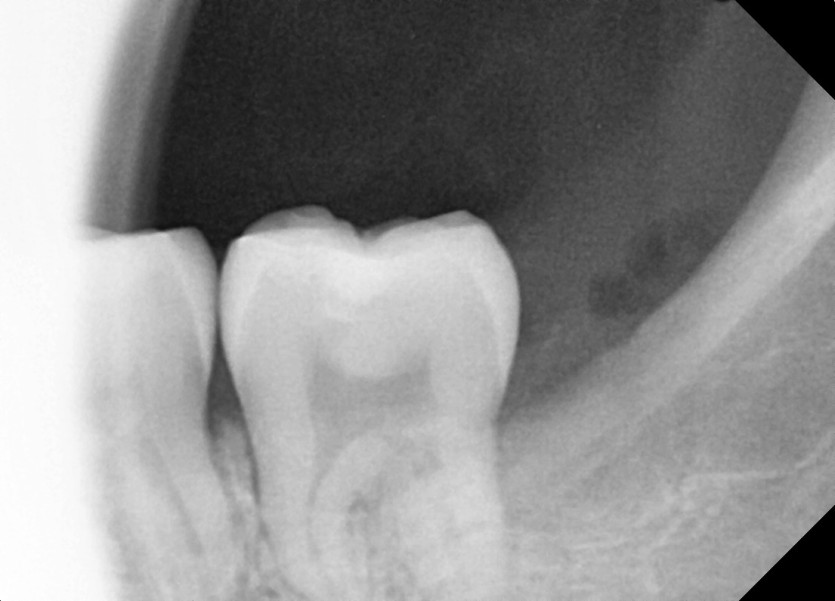

#28,38 사랑니 발치

구강 외과 전문의가 당일 발치했습니다.